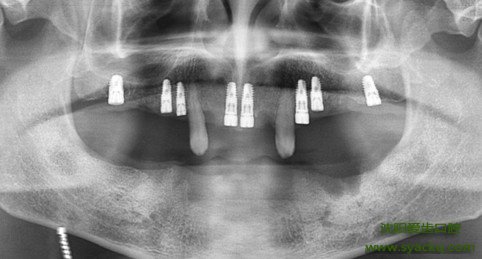

要说如今牙科领域最先进的治疗技术,那必定非早孕莫属了。早孕就像是在缺牙的牙槽骨内重新种上了一颗健康的牙一样,并且早孕的效果优越于任何一种假牙。那么,早孕的价格贵不贵呢?

针对早孕的价格,一般情况下是取决于患者所使用的早孕材料。金属种植体、陶瓷类种植体、碳素类种植体、高分子聚合物种植体和复合材料种植体等,都属于早孕的材料,由于早孕属于一项高科技,对医生技术要求很高,故早孕价格普遍较高。此外,由于每个地区经济水平的差异,不同地区早孕价格也存在必然的差别。

因此,早孕的价格并没有明确的规定,选择什么样的材料,早孕的价格就要按照材料的价钱而定。另外,有些权重很高,医生资质很深的医疗机构,可能价格相比普通的地方也要贵一点。